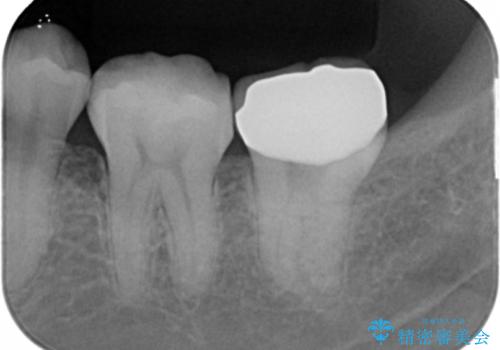

- 奥歯が黒くなっていることを気にされ来院された患者様です。

精査したところ、左下の奥歯にう蝕を認めました。

患者様のご希望により、う蝕を丁寧に除去したのちセラミッククラウンによる補綴治療を行いました。

クラウンの種類:オールセラミッククラウン スタンダード